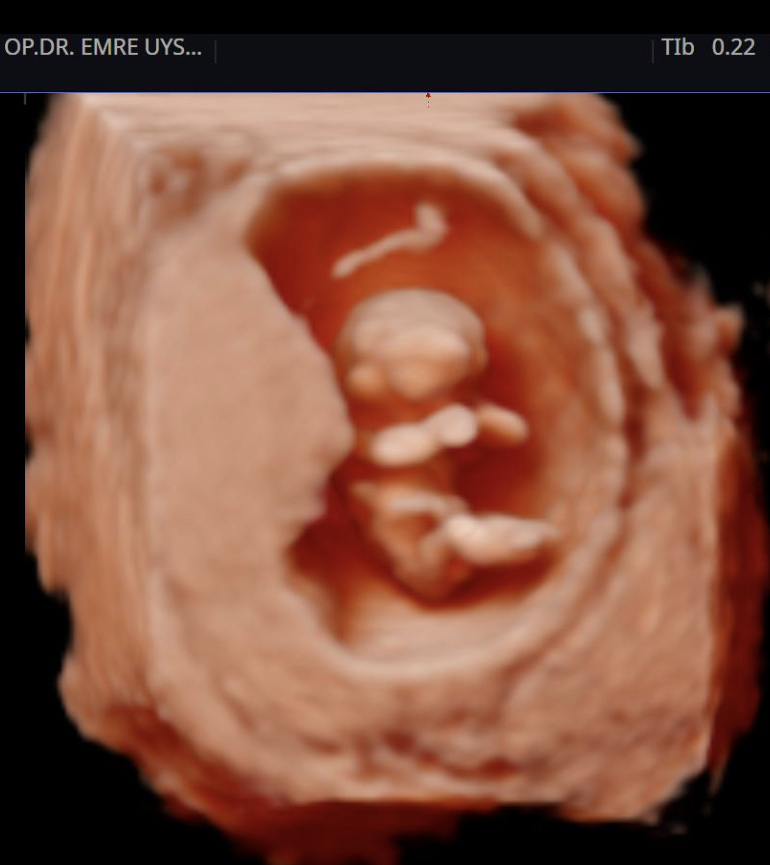

Her kadının hayatında önemli dönüm noktaları vardır. Hiç şüphesizki hamilelik süreci ve doğum bunlardan en kıymetlisidir. Biz de bu değerin farkındayız ve 15 yılı aşan tecrübemiz ile minik mucizenize sağlıkla kavuşma yolculuğunda sizin yanınızdayız. 4d ultrason ile bebeğinizin sağlığını yakından takip ederken, klinik takibimiz ile de süreci eğlenceli ve sağlıklı bir şekilde geçirmeniz için elimizden gelenin en iyisini yapıyor olacağız. Yaşasın Hamilesiniz!